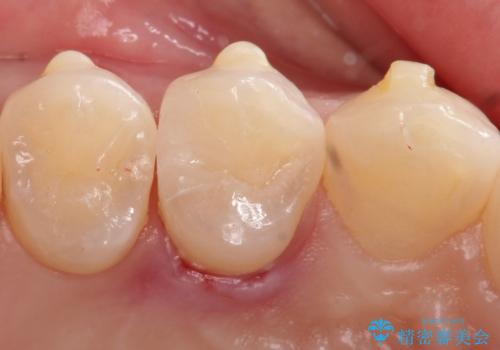

【セラミックインレー】歯と歯の間の虫歯治療

- 歯と歯の間に虫歯が見つかったため、拡大鏡を使用して丁寧に虫歯を除去し、セラミックインレーにて修復治療をおこないました。

セラミックインレーはレジン(プラスチック)と違い、形態の付与がしやすく、長期的な安定性が高い治療です。